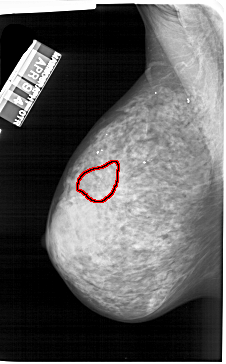

FILE: A_1242_1.LEFT_MLO.OVERLAY

TOTAL_ABNORMALITIES 1

ABNORMALITY 1

LESION_TYPE CALCIFICATION TYPE PUNCTATE DISTRIBUTION CLUSTERED

ASSESSMENT 4

SUBTLETY 2

PATHOLOGY BENIGN

TOTAL_OUTLINES 1

BOUNDARY